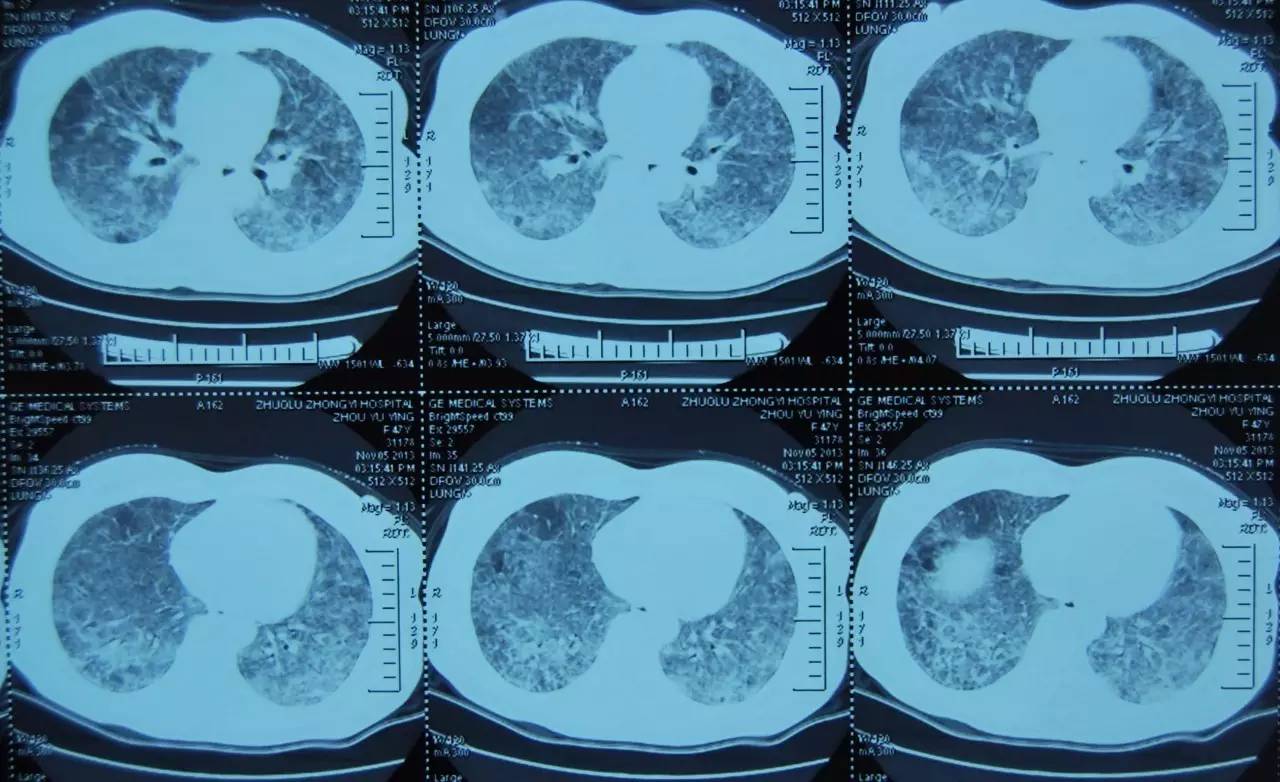

图 1:2013年11月胸部CT

注:双肺弥漫性磨玻璃影及斑片影、可见空气潴留征及小结节影

图 2:2013年11月胸部CT